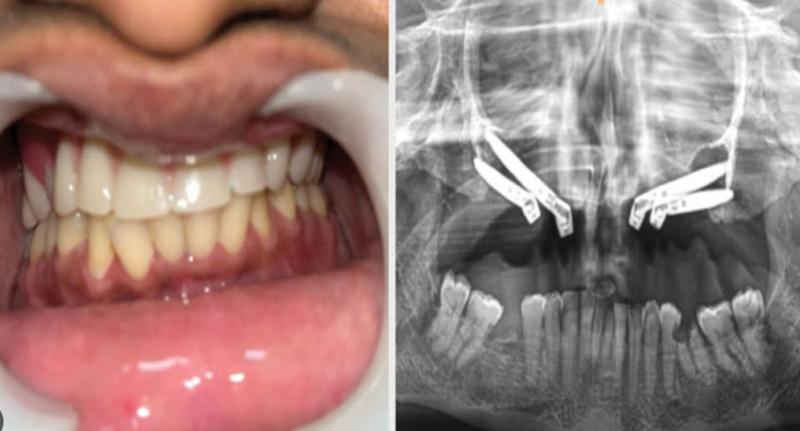

एम्स भोपाल के डेंटल विभाग ने एक बेहद दुर्लभ और जटिल सर्जरी को सफलतापूर्वक अंजाम दिया है। इस सर्जरी में ट्यूमर के कारण काटे गए निचले जबड़े को पैर की हड्डी से दोबारा बनाया गया और उसमें 13 दांत लगाए गए। सर्जरी से मरीज के जीवन में नई खुशियां आई है, साथ ही चिकित्सा के क्षेत्र में एक बड़ी कामयाबी मानी जा रही है। 24 वर्षीय एक युवती मुंह में सूजन और बार-बार पस बनने की समस्या लेकर एम्स भोपाल आई थी। जांच में पता चला कि उसे बिनाइन ओडोन्टोजेनिक ट्यूमर नामक बीमारी है। गंभीर स्थिति को देखते हुए डॉ. अंशुल राय और उनकी टीम में शामिल डॉ. बाबूलाल, डॉ. ज़ेनिश, डॉ. सुदीप, डॉ. फरहान, डॉ. प्रधा और डॉ. दीपा ने बहु-चरणीय सर्जरी करने का निर्णय लिया।

चिकित्सकों के अनुसार पहले चरण में युवती के निचले जबड़े को काटकर ट्यूमर को पूरी तरह हटाया गया। ट्यूमर का आकार 12 सेंटीमीटर से अधिक था और उसके साथ 13 दांत भी निकालने पड़े। इस वजह से जबड़ा कमजोर हो गया और दांत भी नष्ट हो गए थे। जबड़ा और दांत निकल जाने के बाद युवती को भोजन करने में कठिनाई होने लगी, चेहरा विकृत हो गया और वह अवसाद से जूझने लगी। ऐसे में डॉ. अंशुल राय और उनकी टीम ने पैर की हड्डी (इलिएक क्रेस्ट) से नया जबड़ा बनाकर उसमें 9 डेंटल इम्प्लांट्स लगाए। इसके साथ ही, टीम ने मरीज को मानसिक रूप से मजबूत बनाने के लिए लगातार काउंसलिंग सेशन भी किए।

लगभग 6 महीने बाद जब पैर की हड्डी निचले जबड़े से पूरी तरह जुड़ गई, तब युवती के नए दांत लगाए गए। सर्जरी पूरी होने के बाद मरीज का चेहरा पहले जैसा हो गया, खाने-पीने की समस्या खत्म हो गई और उसका आत्मविश्वास लौट आया। अब वह सामान्य जीवन जी पा रही है और उसकी जीवन-गुणवत्ता पहले से कहीं बेहतर हो गई है।

एम्स भोपाल के डॉ. अंशुल रायने बताया कि 20 साल में मध्य भारत में पहली बार 12 सेंटीमीटर का जबड़ा पैर की हड्डी से बनाकर 13 दांत लगाने का यह सफलता मिली। इस अनोखे केस को इंटरनेशनल इम्प्लांट्स जर्नल में प्रकाशन के लिए भेजा गया है। डॉ. राय ने कहा कि सबसे बड़ी सफलता यह रही कि लंबे समय से अवसाद में रह रही युवती फिर से सामान्य जीवन की ओर लौटी और उसके चेहरे पर मुस्कान लौट आई।